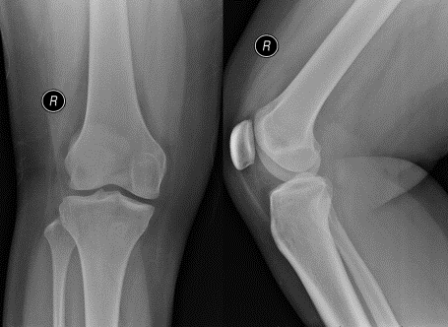

On examination, she was walking with an antalgic gait. Knee effusion was clinically detected. No focal bony tenderness. Knee range of motion was slightly restricted. The knee was grossly stable. Radiograph of right knee was performed.

Q. What are your thoughts on the findings of the knee radiograph?

Normal bony contour. No fracture noted. Raised suprapatellar fat pad suggesting intra-articular knee effusion.